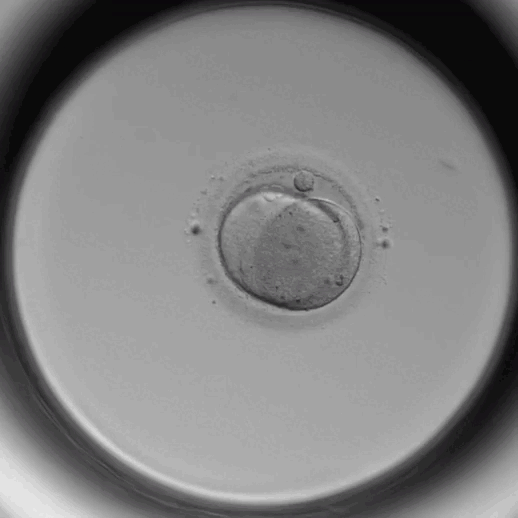

时差培养箱是利用延时摄影技术,全天候24小时监测胚胎的发育过程,记录胚胎发育过程中的各种参数信息,将胚胎几天的培养过程浓缩到数分钟内的高清视频中。这将提高医生对胚胎评估和选择的准确性。

不需要将胚胎反复拿出培养箱观察,在培养箱的显示器上即可直接看到胚胎发育情况,为胚胎提供更稳定的培养环境,获得更多可利用的胚胎和囊胚。

培养箱一天24小时拍摄胚胎照片。在此基础上,医生可以仔细观察胚胎从受精到囊胚形成的完整发育过程,从而得知胚胎发育过程中可能出现的异常分裂现象,为挑选胚胎提供更详细的依据。